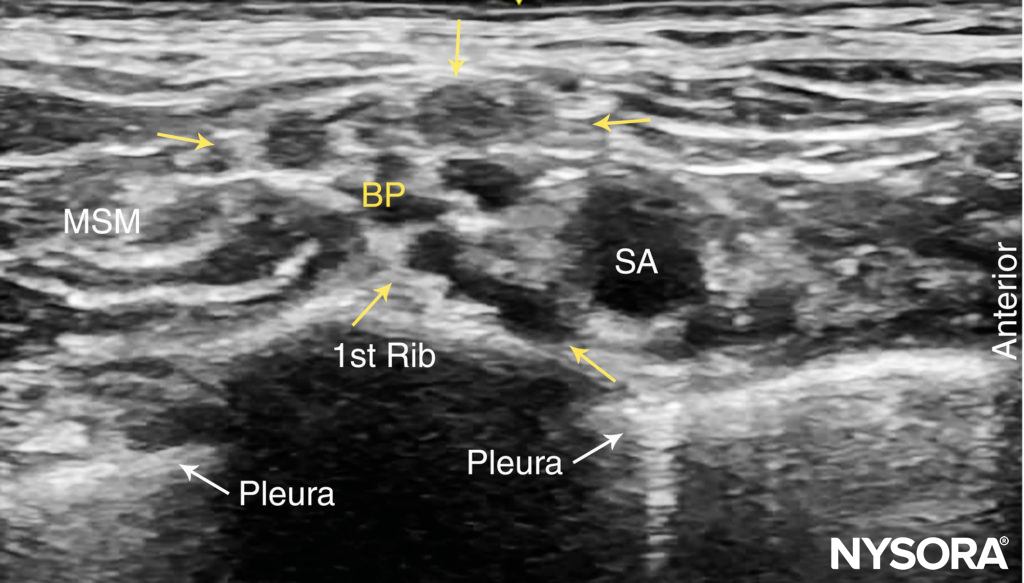

The subclavian artery crosses over the first rib between the insertions of the anterior and middle scalene muscles, posterior to the midpoint of the clavicle. The subclavian artery is readily apparent as an anechoic round structure, whereas the parietal pleura and the first rib can be seen as a linear hyperechoic structure immediately lateral and deep to the subclavian artery (Figure 3). The rib casts an acoustic shadow so that the image field deep to the rib appears anechoic.2 The brachial plexus can be seen as a bundle of hypoechoic round nodules just posterior and superficial to the artery (Figures 3 and 4). It is often possible to see the fascial sheath of the muscles surrounding the brachial plexus. Adjusting the transducer orientation, the upper, middle and lower trunks of the brachial plexus can be individually identified, as they join together at the costoclavicular space. To visualize the lower trunk, the transducer is oriented in the sagittal plane, until the first rib is seen deep to the plexus and the artery. (Figure 4). Anterior or posterior to the first rib is the hyperechoic pleura, with lung tissue deep to it. This structure can be confirmed by observing a “sliding” motion of the viscera pleura in synchrony with the patient’s respiration. The brachial plexus is typically visualized at a 1- to 2-cm depth at this location. The presence of two separate clusters of elements of the brachial plexus may be more or less obvious, sometimes with separation by a blood vessel (Figure 4). The dorsal scapular artery commonly passes through or within the vicinity of the brachial plexus. It is important to recognize that the more superficial and lateral branches come from C5–C7 (shoulder, lateral aspect of arm, and forearm) and can be tracked up to the interscalene area, whereas the deeper and more medial contingent are branches of C8 and T1 (hand and medial aspect of forearm). Adequate spread of local anesthetic in both areas is necessary for successful nerve block of the arm and hand. For additional information see Functional Regional Anesthesia Anatomy.

FIGURE 3. Supraclavicular brachial plexus (BP; yellow arrows) seen slightly superficial and posterolateral to the subclavian artery (SA). The brachial plexus is enveloped by a connective tissue sheath. Note the intimate location of the pleura and lung to the brachial plexus and subclavian artery. MSM, middle scalene muscle.